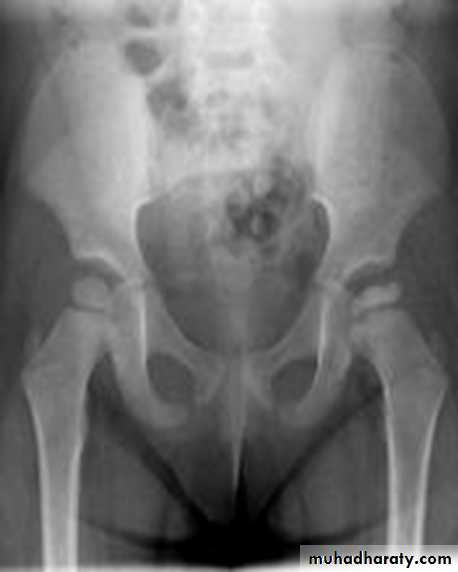

DEVELOPMENTAL DYSFLASIA OF HIP (CONGENITAL DISLOCATION OF THE HIP)

An abnormally lax joint capsule allows the femoral head to fall out of the acetabulum, leading to deformation.

CDH occurs most commonly (70%) in the left hip. Bilateral involvement is seen in 5%.

Radiographic features:

Plain film

At 3-6 months :

By doing special veiw (Von Rosen veiw )by abduction of the thigh 45 degree and internal rotation .

In DDH the lines that drown through the femura will meet in higher level than the normally should at lumbosacral joint .

6 months and later

* AP veiw ( femural epiphysis are visualized ):* Superolateral displacement of proximal femur (disturbed shenton’s line )

* Increase in acetabular angle

* Small capital femoral epiphysis

Femoral head is located lateral to Perkin's line

* Other features that are sometimes present

Abnormal sclerosis of the acetabulum

Shallow acetabulum

Formation of a false acetabulurn